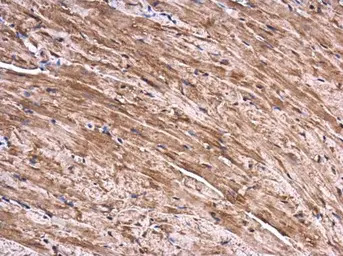

SEC3 antibody [C2C3], C-term detects SEC3 protein at cytoplasm in mouse heart by immunohistochemical analysis.

Sample: Paraffin-embedded mouse heart.

SEC3 antibody [C2C3], C-term (GTX119659) diluted at 1:500.

Antigen Retrieval: Citrate buffer, pH 6.0, 15 min